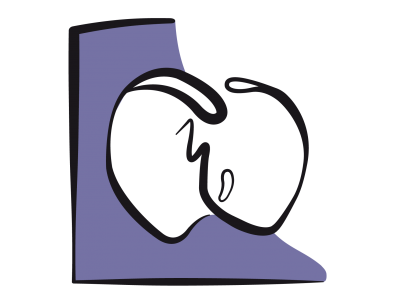

La fonction diastolique représente la capacité du ventricule à accommoder un remplissage adéquat sous un régime de pression basse et sur un vaste éventail de conditions de charge (voir Chapitre 5 La diastole). La dysfonction diastolique se réfère à une anomalie des indices échocardiographiques du remplissage ventriculaire qui reste cliniquement asymptomatique sauf à l'effort majeur, alors que l’insuffisance diastolique, responsable de près de 50% des insuffisances cardiaques congestives, est un syndrome clinique qui se caractérise par une dyspnée et une élévation chronique des pressions de remplissage (POG > 16 mmHg) en présence d’une fonction systolique préservée (FE > 0.5) [2,4]. Dans tous les cas, la pression télédiastolique ventriculaire est plus haute pour un même volume de précharge [2,7]. Une dysfonction diastolique est toujours présente en cas d’insuffisance ventriculaire systolique.

La fonction diastolique représente la capacité du ventricule à accommoder un remplissage adéquat sous un régime de pression basse et sur un vaste éventail de conditions de charge (voir Chapitre 5 La diastole). La dysfonction diastolique se réfère à une anomalie des indices échocardiographiques du remplissage ventriculaire qui reste cliniquement asymptomatique sauf à l'effort majeur, alors que l’insuffisance diastolique, responsable de près de 50% des insuffisances cardiaques congestives, est un syndrome clinique qui se caractérise par une dyspnée et une élévation chronique des pressions de remplissage (POG > 16 mmHg) en présence d’une fonction systolique préservée (FE > 0.5) [2,4]. Dans tous les cas, la pression télédiastolique ventriculaire est plus haute pour un même volume de précharge [2,7]. Une dysfonction diastolique est toujours présente en cas d’insuffisance ventriculaire systolique.